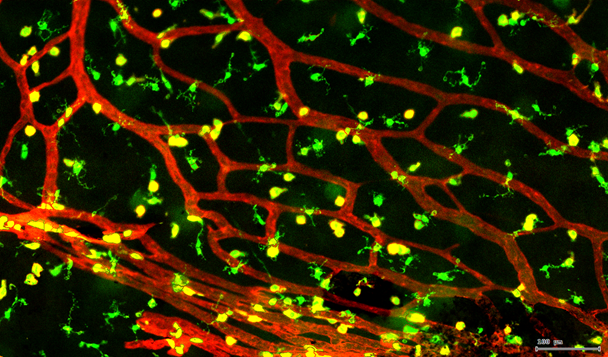

视网膜荧光样本中小胶质细胞胞体、神经纤维识别、血管识别、血管斑点识别、神经元与血管的距离分析。

4. 膜识别FITC染色信号的区域确定神经纤维,并对不同长度神经纤维进行分类。

由于该视网膜样本是标记的小胶质细胞,根据面积将神经胞体分为两类(Small bodycell,Big bodycell),反向回溯Big bodycell中的细胞后,应用Input Gate功能筛选短粗的神经纤维,作为激活态的小胶质细胞。

激活态小胶质细胞识别